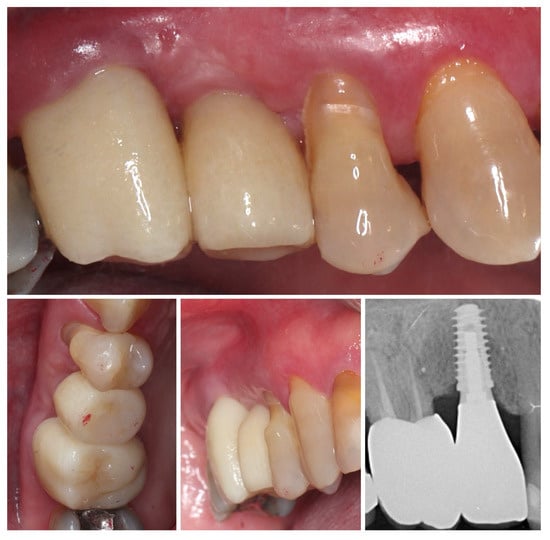

At 4 months after provisional crown placement, clinical examination reveals stable peri-implant soft tissues with a healthy mucosal margin and increased buccal and interdental soft tissue thickness around the temporary crown. The soft tissue integration demonstrates maturation and stability, with no signs of inflammation, recession, or dehiscence. Radiographic evaluation (right) confirms proper implant positioning with intimate bone-to-implant contact and preservation of crestal bone levels, indicating successful osseointegration and tissue stability at this stage of provisionalization (Figure 15.).

Figure 15.

Clinical and radiographic evaluation at 4 months with provisional crown (7 months post-op).

Clinical views of the implant site prior to final prosthetic restoration show a well-formed peri-implant mucosal collar with healthy soft tissue contours. The buccal mucosa demonstrates adequate thickness, consistent with the roll flap augmentation performed at the time of implant placement. The soft tissue margin appears stable without signs of inflammation, ensuring favourable conditions for the subsequent impression and definitive crown placement (left). The comparison with the situation before placement of the provisional crown (right) shows the increase in the soft tissue volume induced by the emergence profile of the crown (Figure 16).

Figure 16.

Peri-implant mucosal contours prior to definitive restoration (8 months post-op).